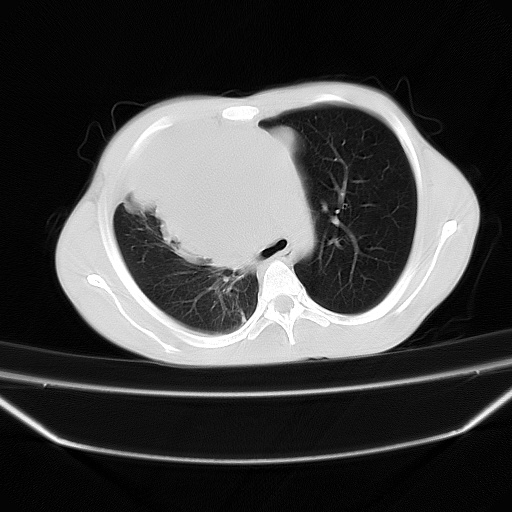

以下是引用zjzjr在2008-7-20 12:57:00的发言:[br]考虑为生殖源性肿瘤(内胚窦瘤),侵袭性胸腺瘤可能性大;右侧少量胸腔积液。

以下是引用xinliheng001在2008-7-20 21:17:00的发言:[br]右纵隔巨大分叶状软组织均质密度肿块,右上肺叶受压明显,纵隔右移、胸膜受累有少量积液和结节样增厚。应增强扫描一定会有更具诊断价值的信息。

以下是引用xinliheng001在2008-7-20 21:17:00的发言:[br]右纵隔巨大分叶状软组织均质密度肿块,右上肺叶受压明显,纵隔右移、胸膜受累有少量积液和结节样增厚。应增强扫描一定会有更具诊断价值的信息。